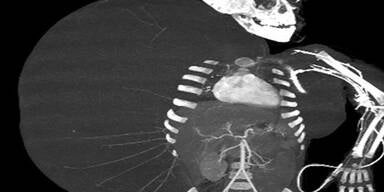

Der 16 Kilo-Tumor wurde Jesus in einer 10 stündigen OP wegoperiert.

Jesus Rodriguez (2) aus dem Norden Mexikos wuchs ein 16 Kilo schwerer Tumor aus seiner rechten Seite und das bei gerade einmal 13 Kilo Körpergewicht. Er hatte den Tumor von Geburt an, allerdings wuchs er erst mit der Zeit auf die gigantische Größe.

Dr. Gustavo Hernandez vom Kinderkrankenhaus La Raza berichtet, dass Jesus in einer 10-stündigen Operation von dem Tumor befreit wurde. Es sei das erste Mal gewesen, dass in Mexiko einer Person ein Tumor entfernt wurde, der schwerer war, als die Person selbst, erklärt Hernandez weiter. Dem Buben geht es nach der Operation den Umständen entsprechend gut.